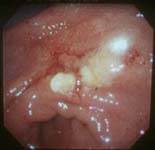

早期食道がん |

進行食道がん |